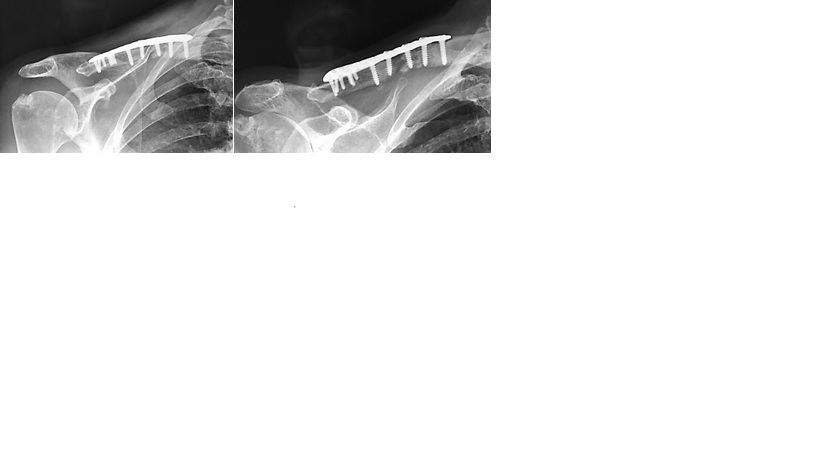

Claviculectomía total como procedimiento de rescate. Reporte de un caso y revisión bibliográfica. [Total claviculectomy as a rescue procedure. Case report and literature review.]